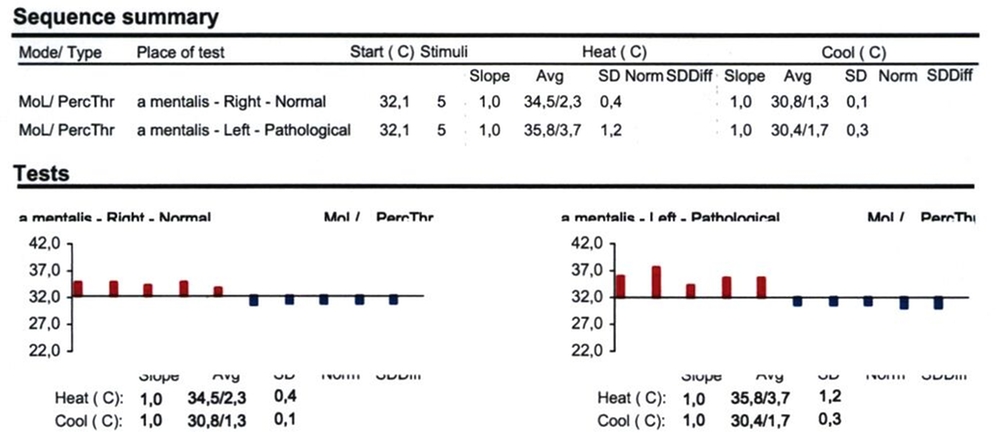

Eine Kontrolluntersuchung zwei Monate postoperativ zeigte einen unauffälligen Heilungsverlauf. Die Hypästhesie des linken Nervus alveolaris inferior war im Wärme-/Kältetest, durchgeführt mit einem NeuroSensory Analyzer (TSA-Test), noch objektivierbar, aber deutlich regredient (Abbildung 4c). Eine weitere röntgenologische Untersuchung sieben Monate nach Operation zeigte eine zunehmende Verknöcherung der Resektionshöhle ohne Rezidivverdacht. Der intraorale Befund war reizfrei und die Sensibilität nahezu vollständig wiederhergestellt (Abbildung 5).